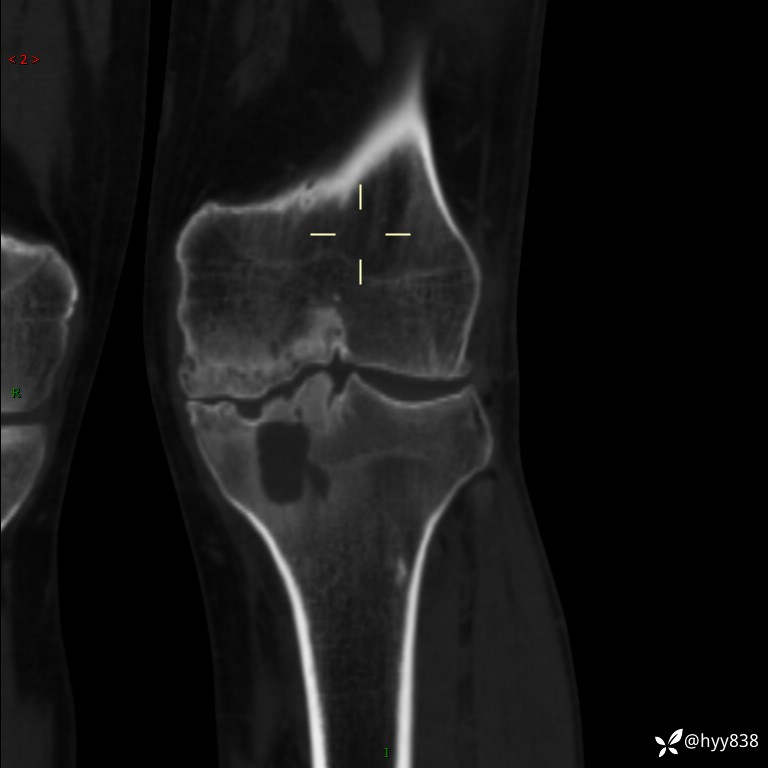

CT